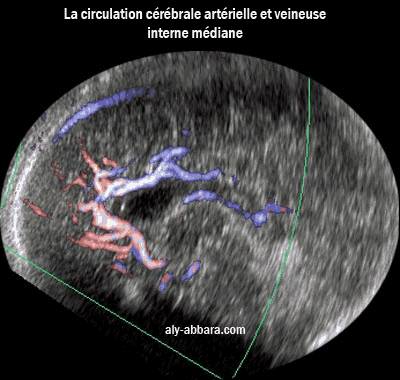

Coupe sagittale médiane du cerveau fœtal à 36 SA

montrant la circulation artéreille et veineuse interne médiane

Image montrant le système de vascularisation cérébrale médiane, artérielle et veineuse

L'artère cérébrale postérieure, l'artére cérébrale antérieure devenant l'artère péricalleuse

et en arrière la veine cérébrale interne, l'ampoule de Galien, le sinus

droit et le sinus logitudinal supérieur.